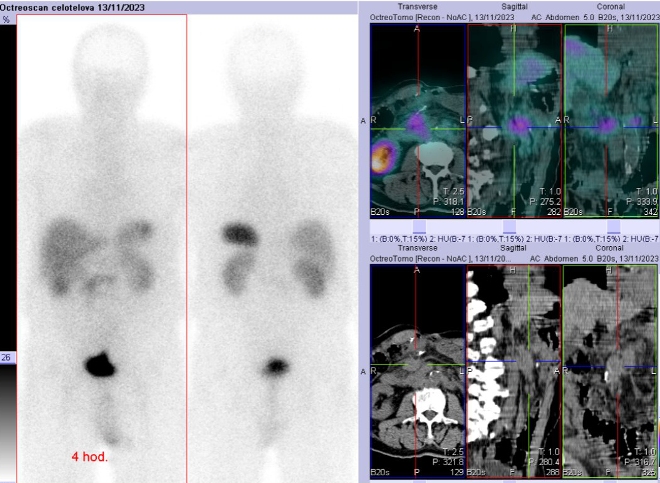

Scintigrafie Octreoscanem:

I. v. jsme aplikovali 190 MBq analogu somatostatinu značeného 111In

(přípravek OctreoScan firmy Mallinckrodt Medical) a provedli pomocí hybridní tomografické scintilační kamery Symbia T2 firmy Siemens opatřené kolimátory pro střední energie planární celotělovou scintigrafii a cílenou tomografickou scintigrafii (SPECT) břicha a pánve kombinovanou s CT za 4 a 24 hod.

(obr. 4-6).

/ Obr. č. 4: Celotělová scintigrafie a fúze SPECT/CT břicha a pánve 4 hod. po aplikaci OctreoScanu.

Závěr: Prokazujeme tři okrsky patologicky zvýšené hustoty somatostatinových receptorů v paketu LU na mesenteriu vpravo ve výši L2, v LU v retroperitoneu paraortálně vlevo ve stejné úrovni a v LU v úrovni L3 vpravo - svědčí pro mts NET. Ve srovnání s vyš. před dvěma roky je nyní navíc patologický nález v uzlině vpravo na úrovni L3, jinak nález beze změn.

Závěr:

Prokázali jsme celkově tři metastázy neuroendokrinního tumoru neznámého origa a to ve třech lymfatických uzlinách, oproti předchozímu vyšetření před dvěma roky prokazujeme navíc metastázu v uzlině na úrovni L3.